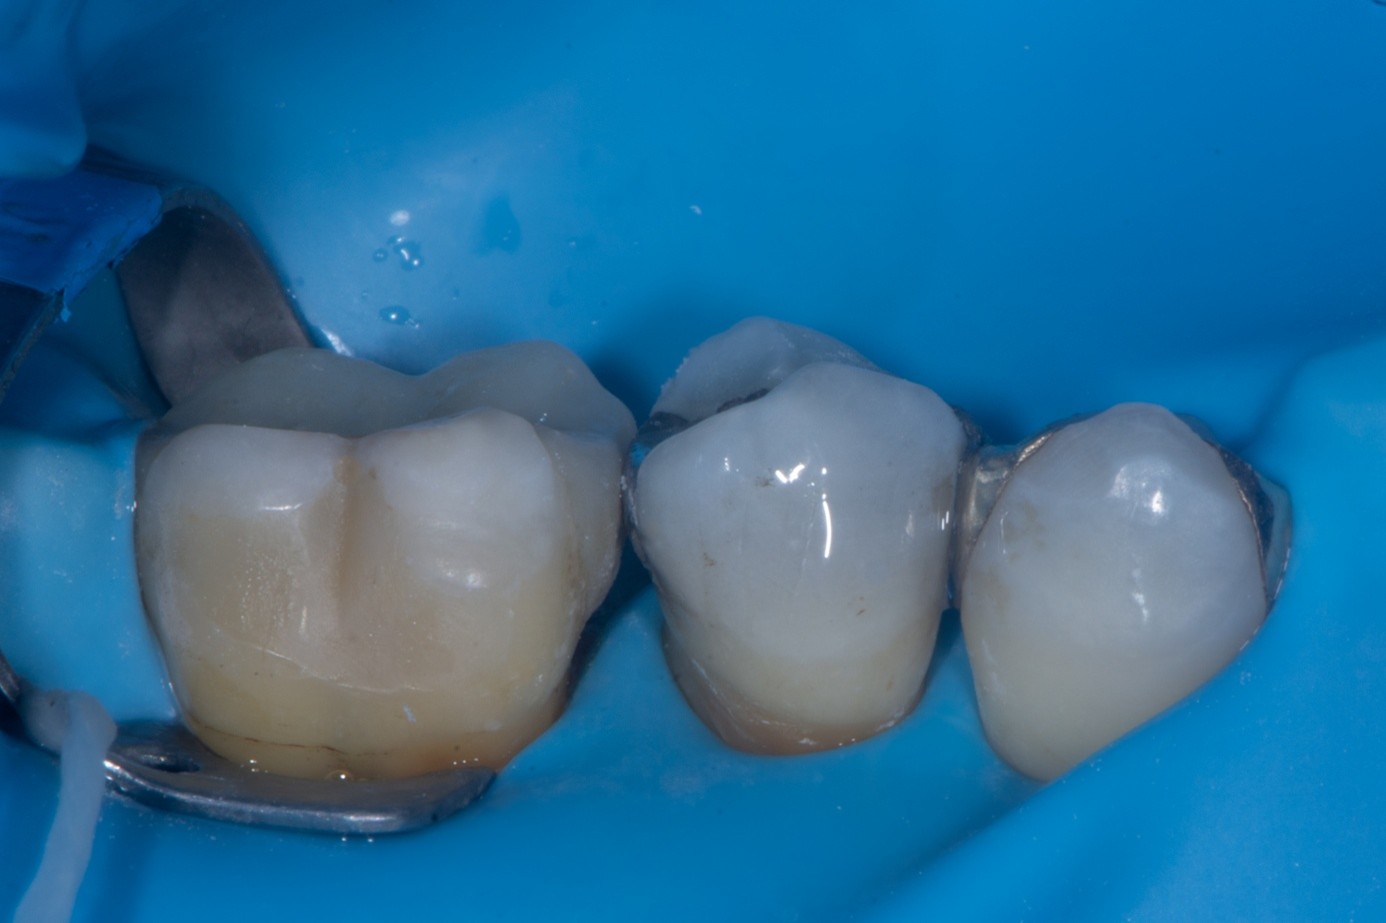

(30.) Intraoral view after absolute isolation with a rubber dam, showing the prepared tooth surface cleaned and roughened with sandblasting, ready for adhesive application and bonding to the crown.

Figure 30